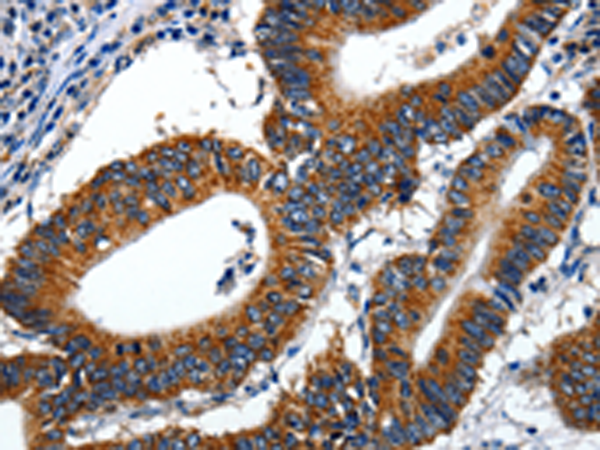

分类: 科研抗体货号: P11004别名: LIG1; LIG-1应用: WB,IHC反应种属: Human, Mouse